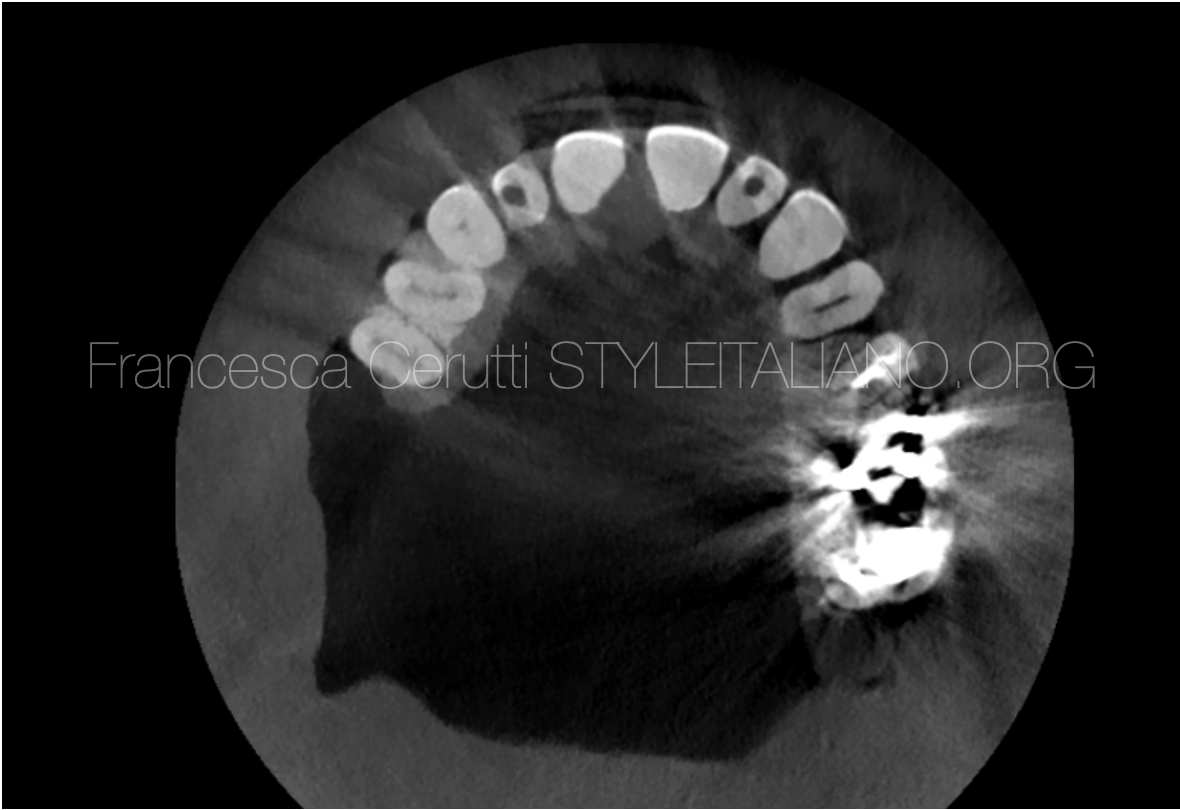

CBCT guided treatment planning and management of instrument fracture in the mesial root of a second mandibular molar

CBCT guided treatment planning and management of instrument fracture in the mesial root of a second mandibular molar

Instrument fracture can be a very frustrating complication in Endodontics. Many factors determine whether a separated instrument should be removed or not from the root canal system. The aim of […]